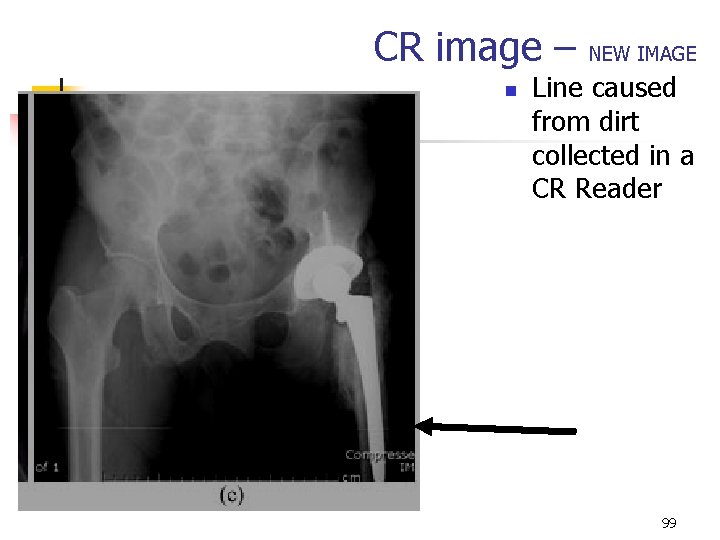

CR image – n NEW IMAGE Line caused from dirt collected in a CR Reader 99